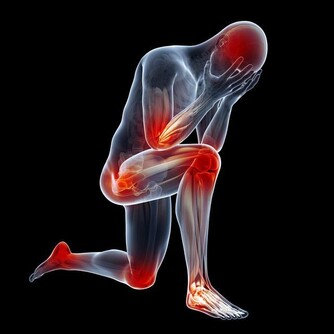

肩部疼痛是臨床常見病症,很多人都曾經歷過,肩膀痛最常見的原因是肩周炎,現在我們來聊聊它吧!

三、肩周炎有哪些表現及如何診斷?1.肩部疼痛:病初肩部呈陣發性疼痛,多數為慢性發作,以後疼痛逐漸加劇或頓痛,或刀割樣痛,且呈持續性,氣候變化或勞累後加重,疼痛可向頸項及上肢放射(此時須與頸椎病鑑別),肩痛晝輕夜重為其特點。

2.肩關節活動受限:肩關節向各方向活動均可受限,以外展、上舉、內外旋更為明顯,特別是梳頭、穿衣、洗臉、叉腰等動作均難以完成。

3.怕冷:患肩怕冷,不少患者終年用棉墊包肩,即使在暑天,肩部也不敢吹風。

4.壓痛:多數患者在肩關節周圍可觸到明顯的壓痛點。

5.肌肉痙攣與萎縮:三角肌、岡上肌等肩周圍肌肉早期可出現痙攣,晚期可發生廢用性肌萎縮,此時疼痛症狀反而減輕。